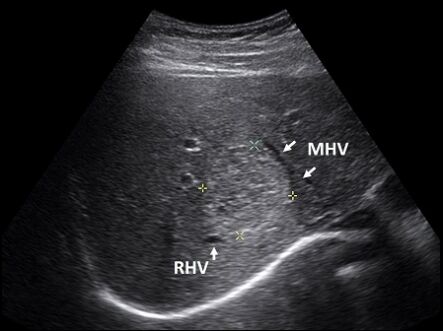

62.肝臟超音波橫向掃描時,發現一個高回音性病灶,介於右肝靜脈(right hepatic vein, RHV)與中肝靜脈(middle hepatic vein, MHV)之間(如下圖)。根據Couinaud classification的分 類,此病灶應在肝臟的那一個節段(segment)? (A)8(VIII) (B)7(VII) (C)4(IV) (D)3(III)